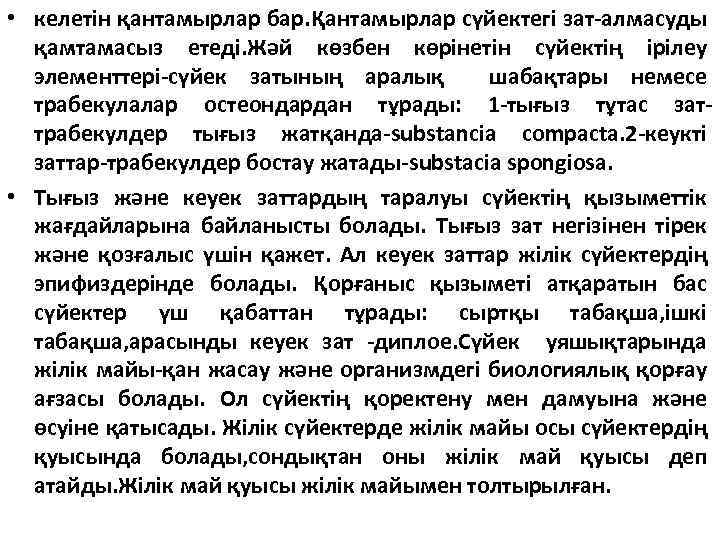

Сүйек ағза ретінде Сүйектердің негізін остеондар немесе Гаверс жүйесі құрайды. Гаверс системасы –өз қан тамырлары мен нерв ташықтары бар. Гаверс өзегін жағалай сақиналы оранасқан сүйек табақшалары. Гаверс өзегі көптеген тамыр тесіктерінен басталады да, сүйекке өзек арқылы енеді, ондай өзектерді фолькман өзектері деп атайды. Остеондар тығыз жабысып жатпайды, олардың арасы сүйек пластикаларымен толтырылған. Остеондар жүйесіз емес, сүйекке түсетін функционалдік жүктемеге сәйкес орналасады: жілікті сүйектерде сүйектің ұзын бойына параллель, кемікті сүйектерде-вертикалді білікке перпендикулярлы; бас сүйектің жалпақ сүйегіне сүйек бетіне параллі және сақиналы орналасады. Остеондар аралық жасаушалармен бірге ішінен эндоост жағынанн сүйек қоршайтын табақшаларының ішкі қабатымен, ал сыртынан периост жағынан қоршайтын табақшалардың сыртқы қабатымен жабылған сүйек затының негізгі ортанғы қабатын түзеді. Сыртқы қабатта сүйек қабының сүйек затына тесіп отетін ерекше жолдар арқылы

• келетін қантамырлар бар. Қантамырлар сүйектегі зат-алмасуды қамтамасыз етеді. Жәй көзбен көрінетін сүйектің ірілеу элементтері-сүйек затының аралық шабақтары немесе трабекулалар остеондардан тұрады: 1 -тығыз тұтас заттрабекулдер тығыз жатқанда-substancia compacta. 2 -кеукті заттар-трабекулдер бостау жатады-substacia spongiosa. • Тығыз және кеуек заттардың таралуы сүйектің қызыметтік жағдайларына байланысты болады. Тығыз зат негізінен тірек және қозғалыс үшін қажет. Ал кеуек заттар жілік сүйектердің эпифиздерінде болады. Қорғаныс қызыметі атқаратын бас сүйектер үш қабаттан тұрады: сыртқы табақша, ішкі табақша, арасынды кеуек зат -диплое. Сүйек уяшықтарында жілік майы-қан жасау және организмдегі биологиялық қорғау ағзасы болады. Ол сүйектің қоректену мен дамуына және өсуіне қатысады. Жілік сүйектерде жілік майы осы сүйектердің қуысында болады, сондықтан оны жілік май қуысы деп атайды. Жілік май қуысы жілік майымен толтырылған.

Жілік майы екі түрлі болады: қызыл және сары. Қызыл жілік майы; торлы ттінннен тұратын нәзік қызыл масса түрінде болады, оның тұзақтарында қан жасалуына және сүйек жасалуына тікелей қатысты жасушалық элементер орналасады. Қантамырлар және қан элементері жілік майына қызыл түс береді. Сары жілік майы негізінен май жасаушаларынан тұрғанан кейін сары түсті болады. Іштегі нәресте және туған балада тек қызыл жілік майы болады. Бала өсе келе қызыл жілік майы бірте-бірте сары жілік майына аусысады да, ересек адамда тек сары жілік майы ғана болады. Сүйекті сыртқа жағынан сүйек қабымен жабылған. Ол екі қабаттан тұрады: сыртқы және ішкі сүйек түзуші қабаттардан тұрады. Сүйек қабығы нервтер мен қантамырларға бай, соның арқасында сүйектің қоректену мен қалыңдап өсуіне қатысады. Қоректену сүйек қабының қоректік тесікшелер арқылы өтетін тамырлар есебімен, ал сүйектің өсуі, сүйеккке жанасып жатқан қабатта орналасқан остеобластар есебінен іске асырылады.